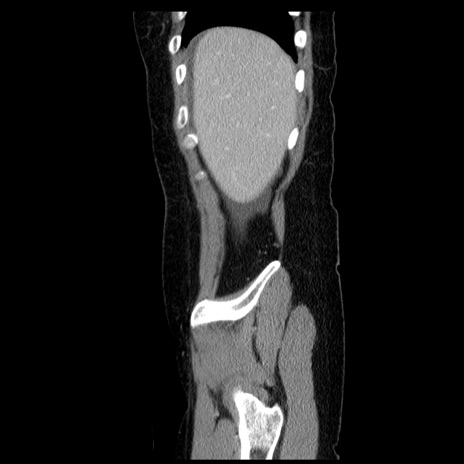

症例6(矢状断像)

【症例】50歳代女性

【主訴】下腹部痛

【現病歴】本日朝より下痢2回あり。 昼食を食べた後、嘔吐3回、下腹部痛認め、症状軽快せず、当院救急搬送。

最終食事:本日昼(生ものなし)。 昨日の夜、刺身を食ぺたとのこと。周囲に同様の症状の者なし。普段、排便は毎日あるとのこと。

【既往歴】卵巣癌術後(8年前に当院で卵巣摘出)

【身体所見】 意識清明、腹部:平坦、腸蠕動音→、やや硬、下腹部自発痛・圧痛あり、反跳痛あり、筋性防御なし。

【データ】WBC 16000、CRP 0.01